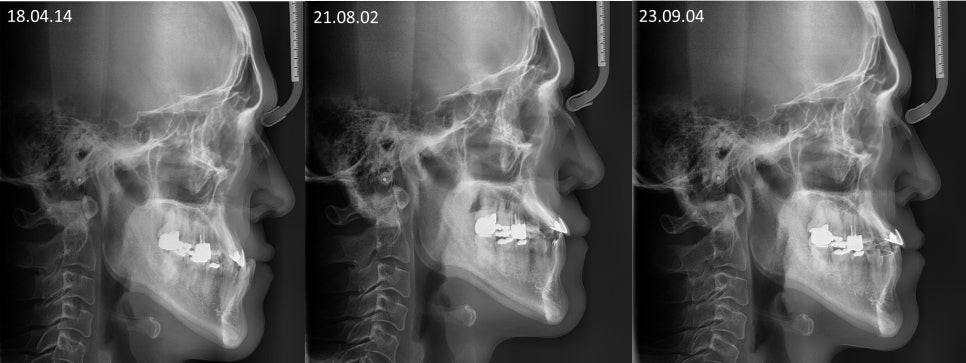

ºñ¼ö¼ú ÁÖ°ÆÅÎ ±³Á¤Ä¡·á ÀüÈÄÀÇ

¿·¾ó±¼ ¿¢½º·¹ÀÌ ÀÔ´Ï´Ù.

ºñ¼ö¼ú ÁÖ°ÆÅÎ ÀüÈÄ ±³ÇÕÀÔ´Ï´Ù.

¾Æ·¡ÅÎÀÌ ¸¹ÀÌ ¾ÕÀ¸·Î ³ª¿ÍÀÖ¾ú´Âµ¥

¾ç¾Ç¼ö¼úÀÌ ¾Æ´Ï¶ó

±³Á¤Ä¡·á ¸¸À¸·Î

±³ÇÕÀÌ Àß °³¼±µÈ °ÍÀ»

º¼ ¼ö ÀÖ½À´Ï´Ù.

ºñ¼ö¼ú ÁÖ°ÆÅÎ ±³Á¤Ä¡·á ÀüÈÄÀÔ´Ï´Ù.

Á¤»ó±³ÇÕÀ¸·Î

°³¼±ÀÌ Àß µÇ¾ú°í

ºñ¼ö¼ú ÁÖ°ÆÅÎ ±³Á¤Ä¡·á ÈÄ

2³âÀÌ °æ°ú µÇ¾îµµ

ÁÁÀº ±³ÇÕÀ» Àß À¯ÁöÇϰí À־

³Ê¹« ´ÙÇàÀÌ¿´½À´Ï´Ù.